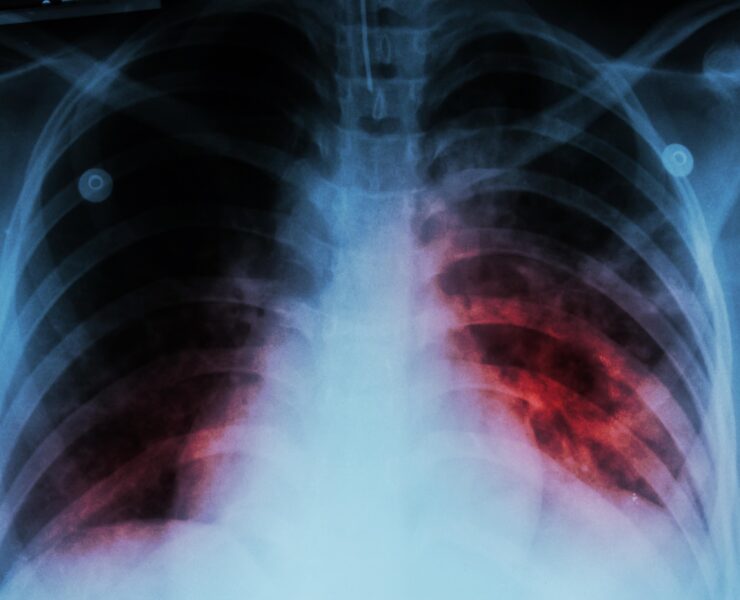

Tuberculosis

La tuberculosis es una enfermedad mundial. Es la principal causa infecciosa de muerte en todo…